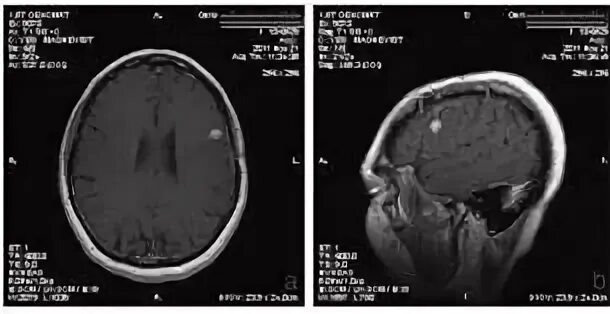

Рак рецидив после операции